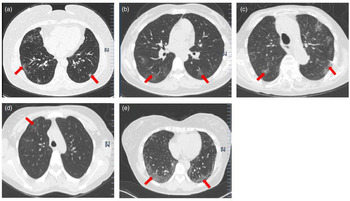

Radiological and laboratory findings

At the time of admission, all the cases had abnormal chest CT findings. As shown in Figure 2, case 1 showed multifocal ground-glass opacity (GGO), predominantly involving subpleural regions of both lung CT scans. Case 2 showed patchy GGO of both lungs. Cases 3 and 5 showed multifocal GGO, especially around the outer bands of the lungs on CT scans, which were compatible with changes observed in viral pneumonia. Case 4 had no clinical symptoms, but chest CT showed patchy GGO in the right upper lobe. As shown in Table 1, all the cases had normal or reduced white blood cell counts, and cases 2–5 developed lymphocytopenia, which was consistent with the main characteristic of viral infection. In terms of inflammation indicators, all the patients on admission presented an elevated serum erythrocyte sedimentation rate (ESR), but no elevated C-reactive protein or procalcitonin. Case 4 had higher levels of bilirubin and lactate dehydrogenase (LDH). The other laboratory test results did not show significant abnormalities.

Fig. 2. Chest CT imaging of case 1 (a), case 2 (b), case 3 (c), case 4 (d) and case 5 (E). (a) CT shows multifocal GGO involving the subpleural regions of both lungs (red arrow). (b) CT shows patchy GGOs of both lungs (red arrow). (c and e) CT shows multifocal patchy GGOs that primarily appear at the peripheral area of both lungs (red arrow). (d) CT shows patchy GGOs in the right upper lobe (red arrow).